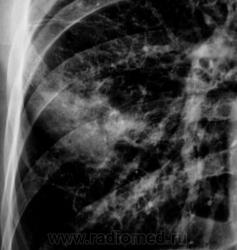

Контроль через 1 месяц после противовоспалительной терапии.